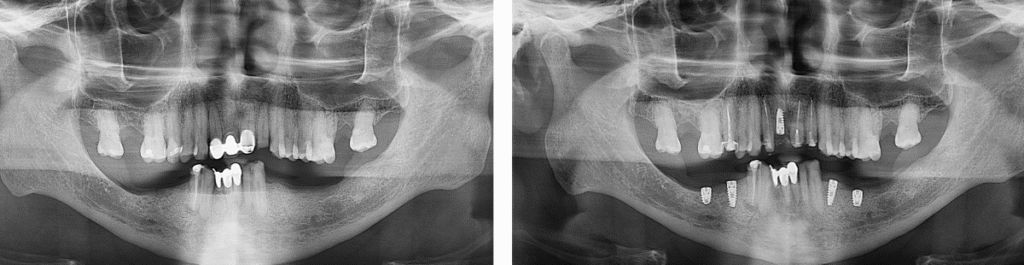

Caso de implantes